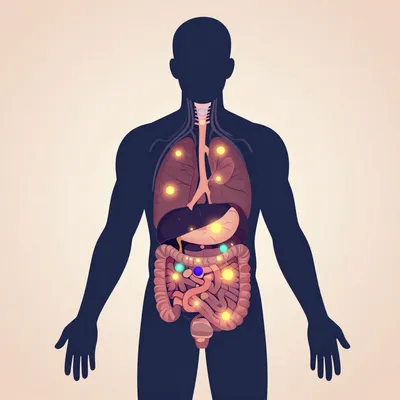

Denna bild skapades av artificiell intelligens. Den är gratis att ladda ner och använda var som helst – webbplatser, tryck, sociala medier, kommersiella projekt.

Gratis

CC0

Kommersiell användning